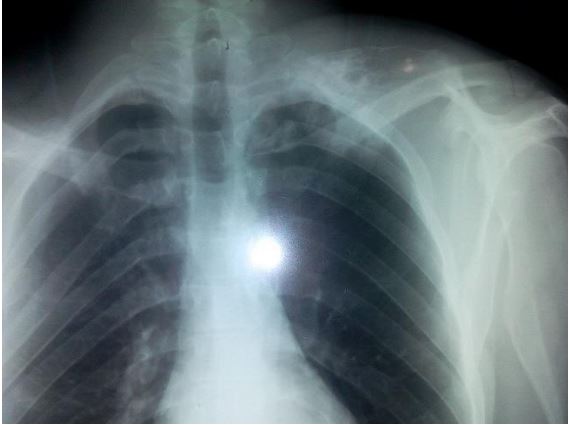

A 24-year-old young man was presented for consultation for a mass on the dorsal side of the scapula that had been present for 3 years. This mass was hard, non-painful and slightly mobile; the scapula formed a voluminous dorsal hump 12 cm long, 8 cm wide and 5 cm thick (Figure 1). This mass led to fatigability of the shoulder during exercise, a limitation of particularly active shoulder joint movements and great aesthetic discomfort. The standard front x-ray of the scapula revealed heterogeneous bone formation at the spinal edge of the scapula (Figure 2). A CT scan confirmed the presence of the large exostosis, the boundaries of which appear regular and corticalized (Figure 3). The patient underwent surgery, with en bloc resection of the tumor and extraction of the detached fragments (Figure 4). The pathological examination concluded that it was an osteochondroma.

Figure 2: Radiological appearance of pedunculated osteochondroma at the edge spinal of the scapula..